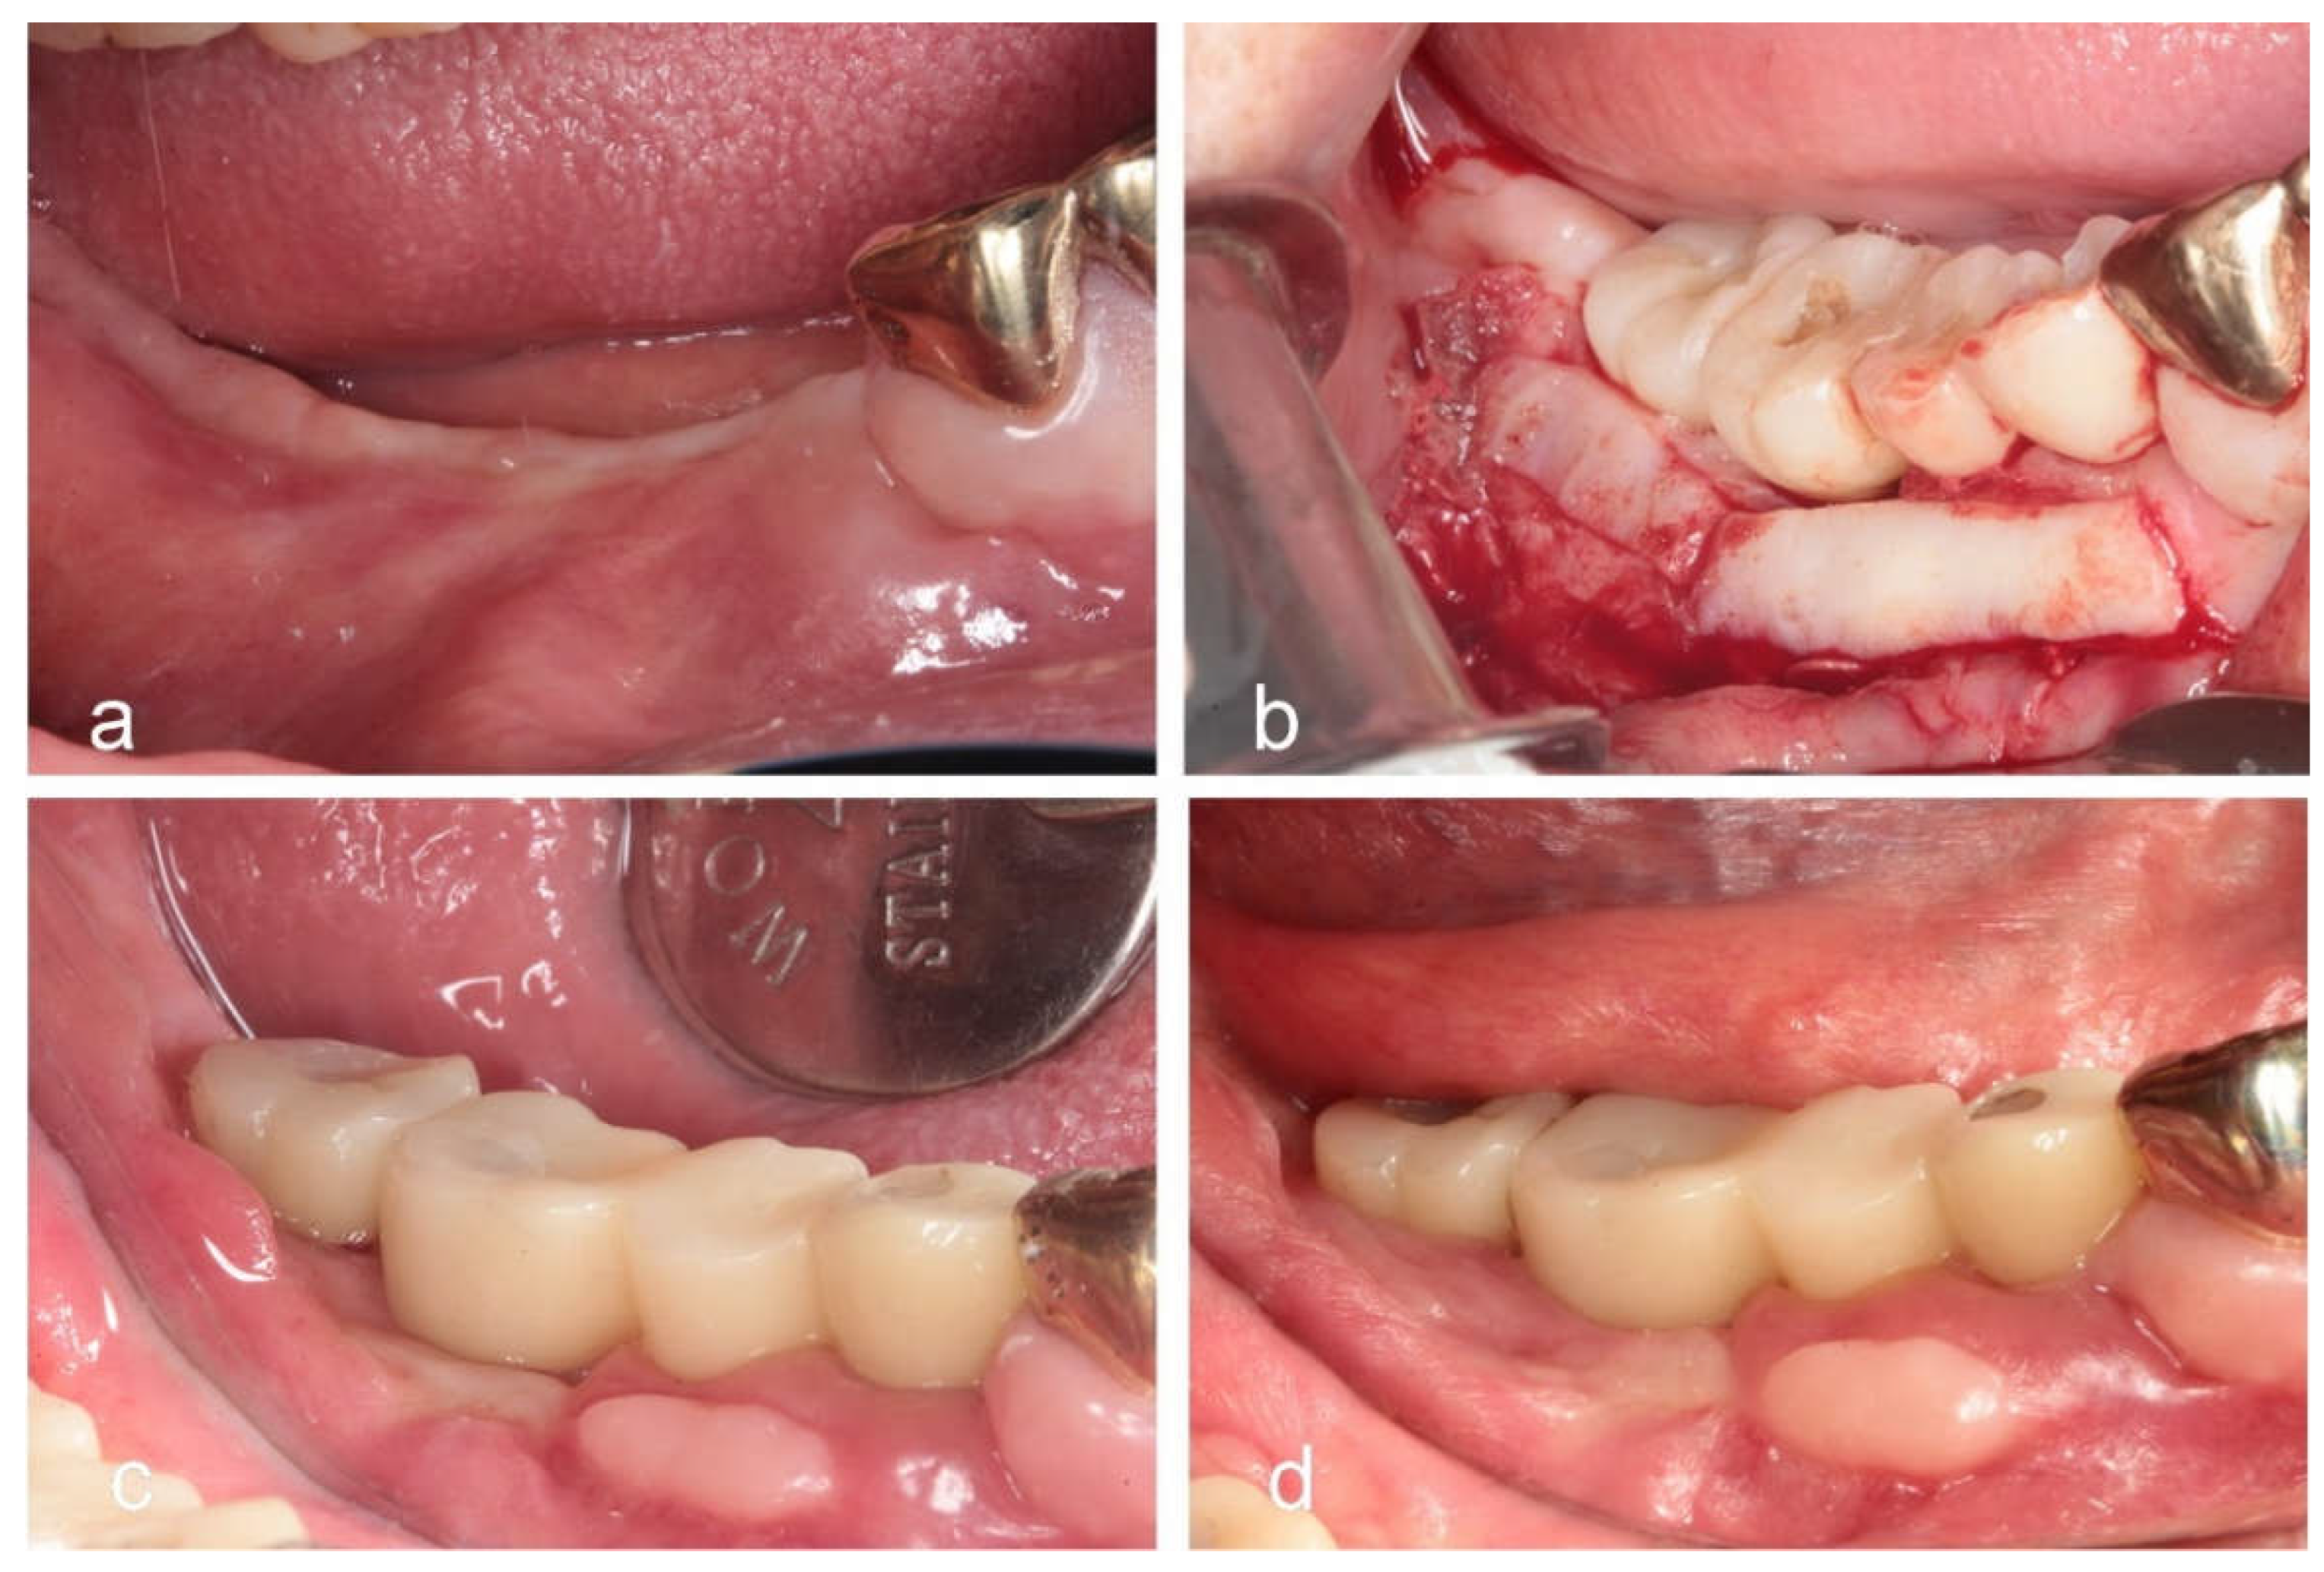

- Menchini-Fabris, G.B.; Cosola, S.; Toti, P.; Hwan Hwang, M.; Crespi, R.; Covani, U. Immediate Implant and Customized Healing Abutment for a Periodontally Compromised Socket: 1-Year Follow-Up Retrospective Evaluation. J Clin Med. 2023, 12, 2783. [Google Scholar] [CrossRef] [PubMed] [PubMed Central]